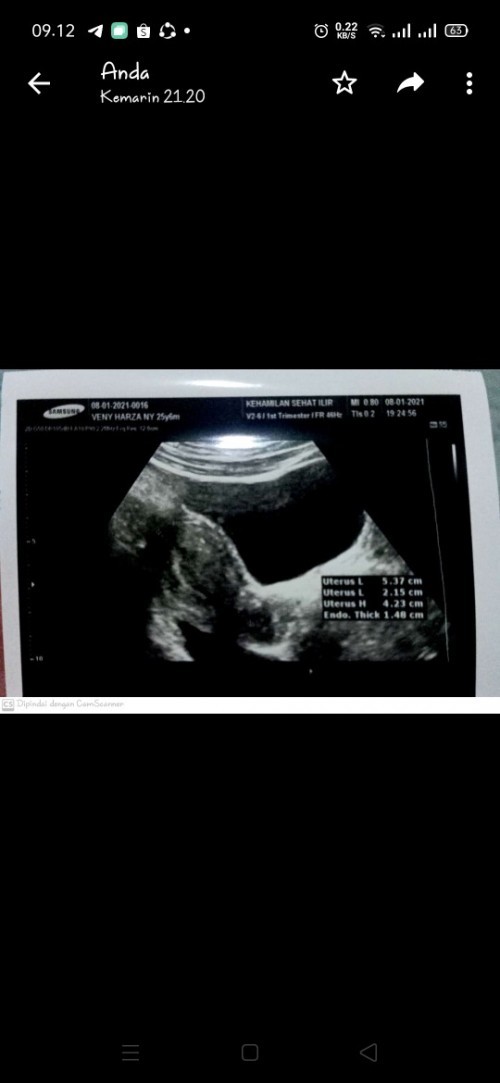

hpht tgl 10 des,TP positif.ke dokter dibilang hamil muda tp janin blm keliatan prnh bgalamin ni bun?

biasanya 2 minggu lagi disuruh balik lagi buat usg